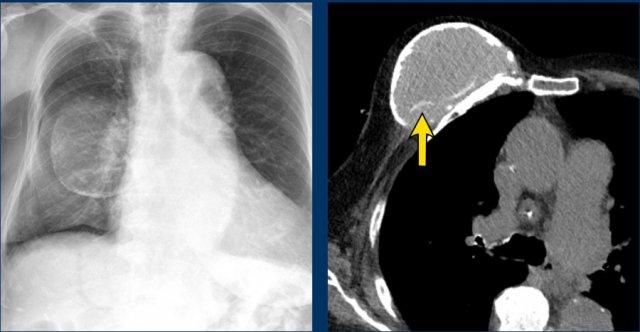

Phim ngực thẳng cho thấy vôi hóa bao xơ trong một túi ngực nhân tạo bị di lệch vào trong, không song song với đường viền tuyến vú.

CT của cùng bệnh nhân này cũng cho thấy vôi hóa ở mặt sau không đi theo đường viền của túi ngực, gợi ý vỡ túi trong bao xơ (mũi tên).